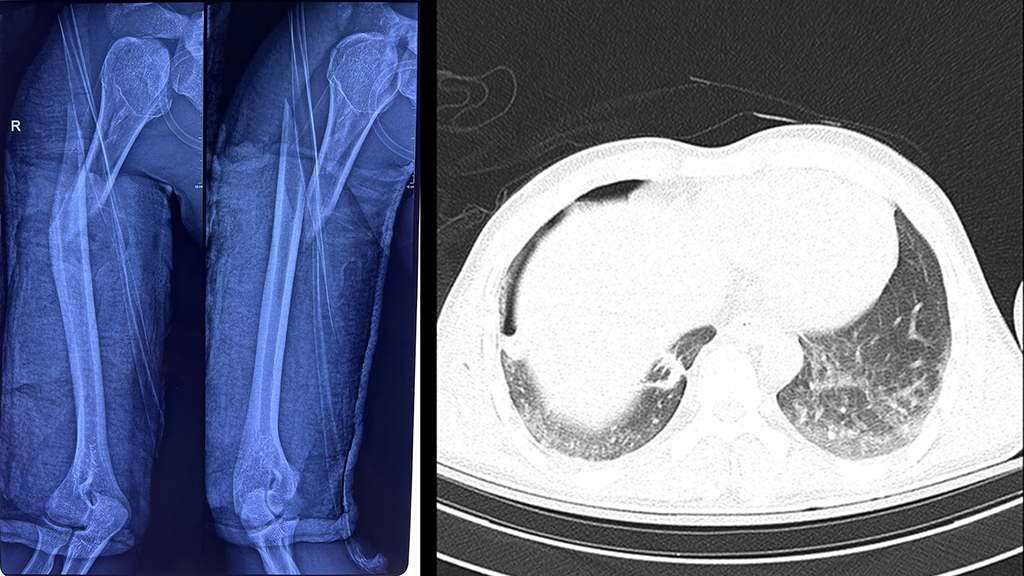

‘Khi tiếp nhận tại khoa ICU, người bệnh suy hô hấp nặng, cánh tay phải biến dạng, bầm tím, có dấu hiệu nhiễm trùng’, BS.CKI Sơn Tấn Ngọc – Chuyên khoa Chấn thương chỉnh hình cho biết. Kết quả X-quang ngực tại giường cho thấy nam thanh niên bị tràn khí màng phổi phải do chấn thương dập phổi nặng, kèm gãy phức tạp đầu trên và gãy chéo dài 1/3 trên xương cánh tay phải.

Xương cánh tay phải của người bệnh bị gãy hoàn toàn, kèm dấu hiệu tràn khí màng phổi.